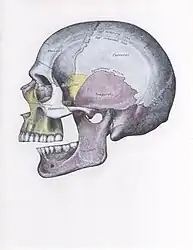

![]() | |

| Sagittal section of the articulation of the mandible. | |

Anatomy

The joint involved with jaw dislocation is the temporomandibular joint (TMJ). This joint is located where the mandibular condyles and the temporal bone meet.[4][6] Membranes that surround the bones help during the hinging and gliding of jaw movement. For the mouth to close it requires the following muscles: the masseter, temporalis, and medial pterygoid muscle. For the jaw to open it requires the lateral pterygoid muscle.[4]